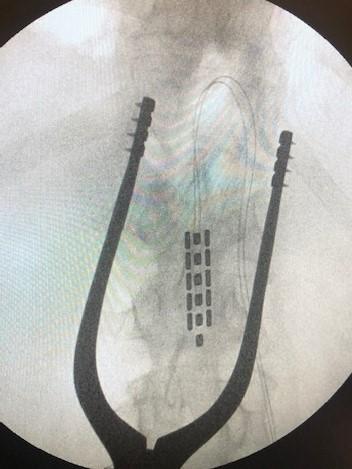

Clinical tools used in the lab include vascular and cardiac ultrasound, beat-by-beat blood pressure, cardiac, cerebral and spinal cord MRI, orthostatic stress testing, exercise stress testing, functional electrical stimulation, passive cycling, arterial blood gas reactivity testing (RespirAct Gen IV), both surgically implanted and non-invasive neurostimulation modalities, eye tracking, muscle sympathetic nervous system recordings, etc. Preclinical tools include various tissue clearing methods (CLARITY, uDISCO) arterial cannulation, nerve recordings, spinal cord transection/contusion, and a variety of genetic strains for manipulation (e.g., Th-Cre, PV-Cre). The lab is also employing a novel computational pipeline for managing large data-sets of physiological metrics.